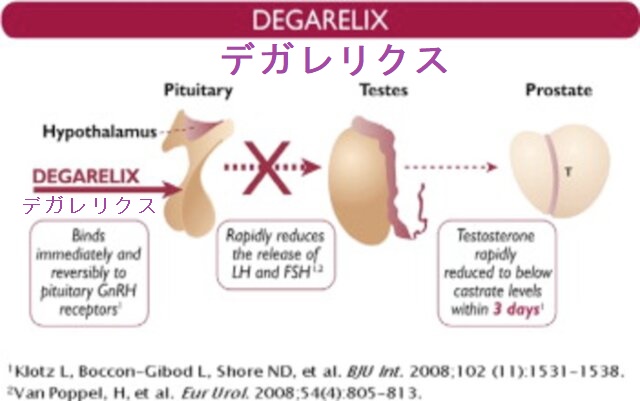

GnRHアンタゴニストのデガレリクス酢酸塩(ゴナックス®)は、前立腺がんのホルモン療法に使用されます。脳下垂体の性腺刺激ホルモン分泌を抑えることで、テストステロン(男性ホルモン)合成を抑制します。 副作用として、頻度不明ながら甲状腺機能異常の報告があります。また、国内第Ⅱ相試験(0009 試験)で甲状腺癌1 例(1.3%)を認めたとされます。

その他の副作用として、糖尿病増悪、血栓症の可能性もあります。